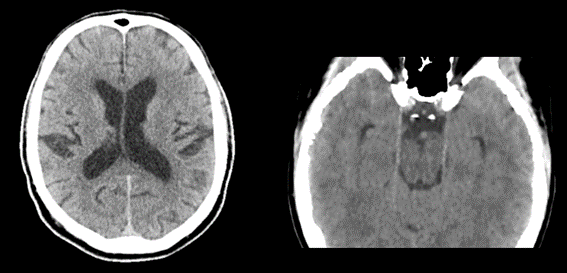

Existen casos donde podremos observar un aumento del espacio subaracnoideo lo cual no debe informarse como patológico o como atrofia yo que el mismo puede simplemente deberse a un hallazgo de naturaleza constitucional.

En relación con la atrofia cortical que es propia de los pacientes añosos, esta no debe confundirse con higromas o hematomas subdurales crónicos.

Fig. 7.

Encontramos como primer error el volumen parcial dado por estructuras vecinas, es frecuente con las estructuras óseas

Los lóbulos temporales y fosa posterior son afectados por artefactos de endurecimiento del rayo y se aprecian como zonas de hipodensidad irregular y no debe confundirse con gliomas. Se diferencian por la falta de masa.

Fig. 10.

Fig. 9.